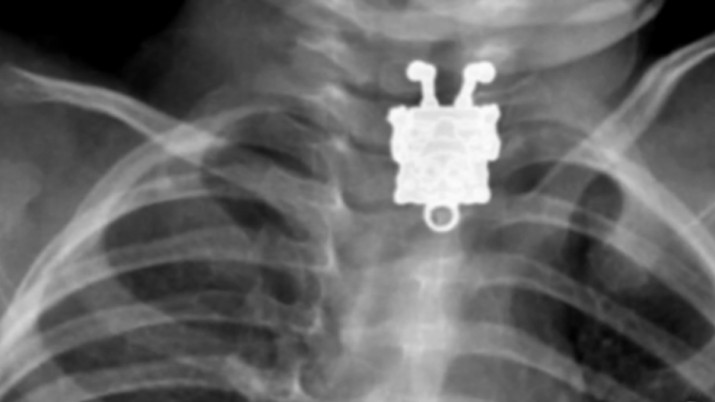

U eri razvoja znanja o nevidljivim zracima, poput radio talasa i zračenja, jedan fizičar je otkrio da kada pumpa struju kroz posebnu cijev – sijalicu, hemijska supstanca udaljena par metara bi zasijala. On je shvatio da cijev šalje nevidljive zrake koje prodiru kroz papir, drvo i čak kožu. Nazvao ih je X zraci (nepoznati). Prvu rendgen – sliku napravio je slikajući ruke svoje supruge koja je, nakon što je vidjela izjavila: “Vidjela sam svoju smrt”.